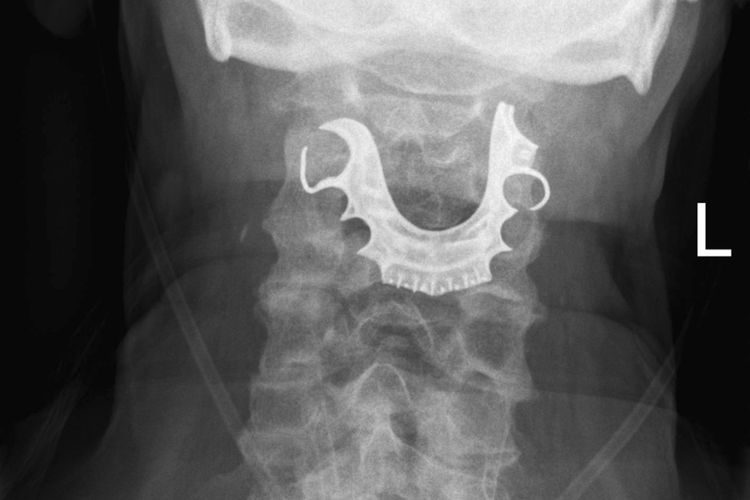

सरळ मुद्द्याला हात घालूया. त्याचं झालं असं, की युकेच्या एका ७२ वर्षांच्या आजोबांवर पोटाची शस्त्रक्रिया करण्यात आली होती. शस्त्रक्रियेच्या ६ दिवसानंतर हे आजोबा पुन्हा हॉस्पिटलमध्ये आले, तेव्हा त्यांच्या घशातून रक्त निघत होतं. त्यांचा घसा दुखत होता, अन्न गिळता येत नव्हतं आणि खोकल्यासोबत रक्त येत होतं. त्यांनी डॉक्टरांना म्हटलं की ऑपरेशन झाल्यापासून त्यांना अन्न गिळता येत नाहीय.